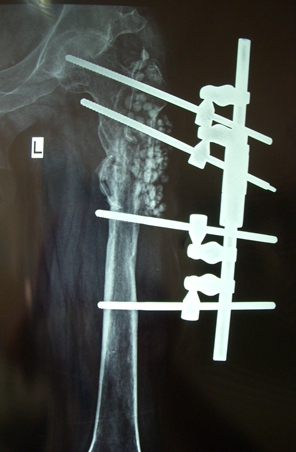

图7.股骨近段骨折后骨髓炎、骨不连的治疗